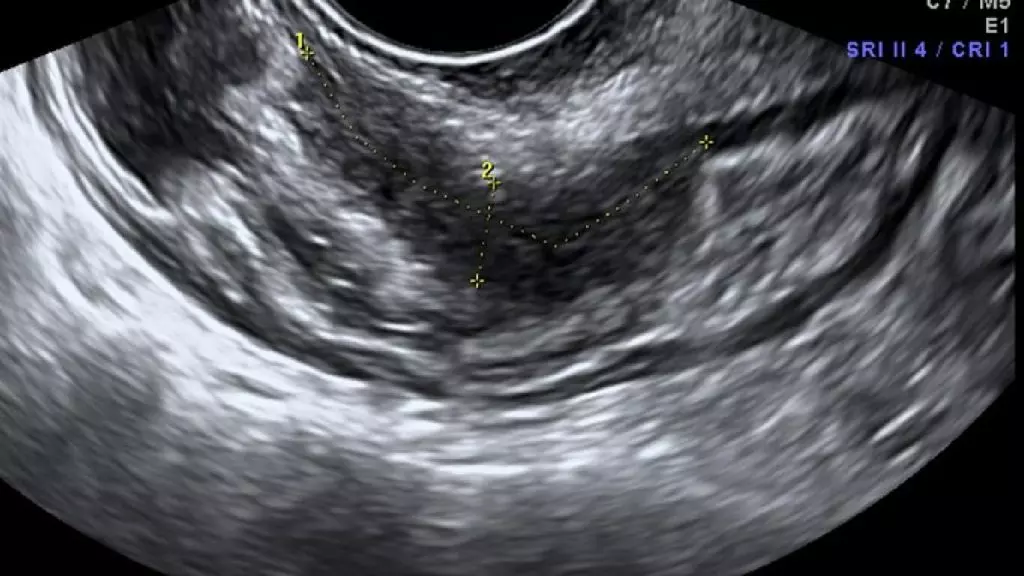

A pesar de su alta prevalencia, el diagnóstico de la endometriosis es particularmente difícil. Actualmente, la cirugía laparoscópica es el estándar para confirmarla, lo que implica insertar una cámara en el abdomen para buscar tejidos anómalos. Este procedimiento, aunque efectivo, es invasivo, costoso y no siempre accesible. En países como Australia, las mujeres pueden esperar hasta siete años para obtener un diagnóstico definitivo, tiempo en el cual la enfermedad puede empeorar y limitar opciones de tratamiento.

Este avance es crucial, ya que permite detectar la endometriosis incluso en etapas tempranas, algo que los métodos actuales como ecografías o resonancias magnéticas no logran con precisión en todos los casos. Según el coautor del estudio, el Dr. Richard Lipscombe, esta prueba no solo es más accesible, sino también más rentable, tanto para las pacientes como para los sistemas de salud.